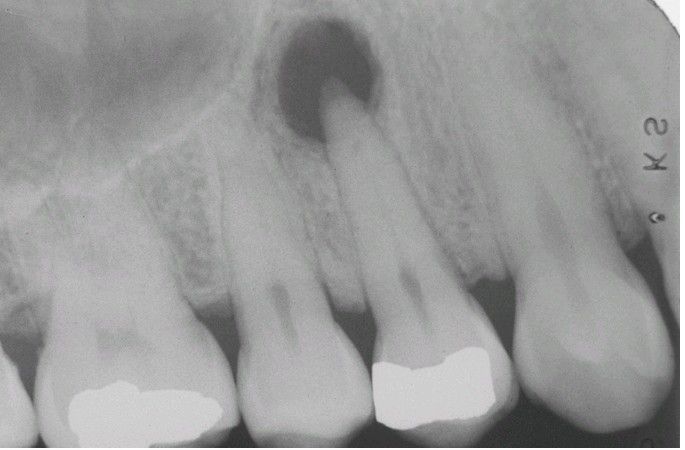

Periapical Granuloma

. Well-defined radiolucency associated with the apex of the maxillary first bicuspid.